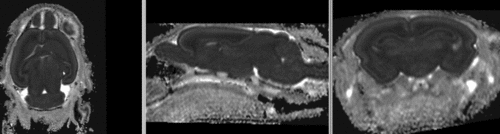

affine registered brains affine registered